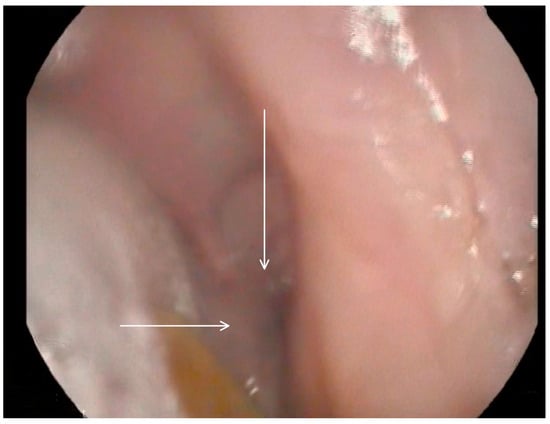

Following these findings, the ENT specialist reassessed the patient and confirmed the presence of bilateral diverticula in the buccal area and posterior pharyngeal walls, in alignment with the VFSS findings. The two diverticula were located on the right and left side inferiorly in the buccal area (Figure 3) and (Figure 4), and two were located on the right and left side superiorly in the oropharynx area. (Figure 5) and (Figure 6).

Figure 5. Selected still image captured during the FEES assessment: arrow heads pointing to the opening of a diverticulum located in the left superior aspect of the oropharynx area.

Medicina 60 01628 g005